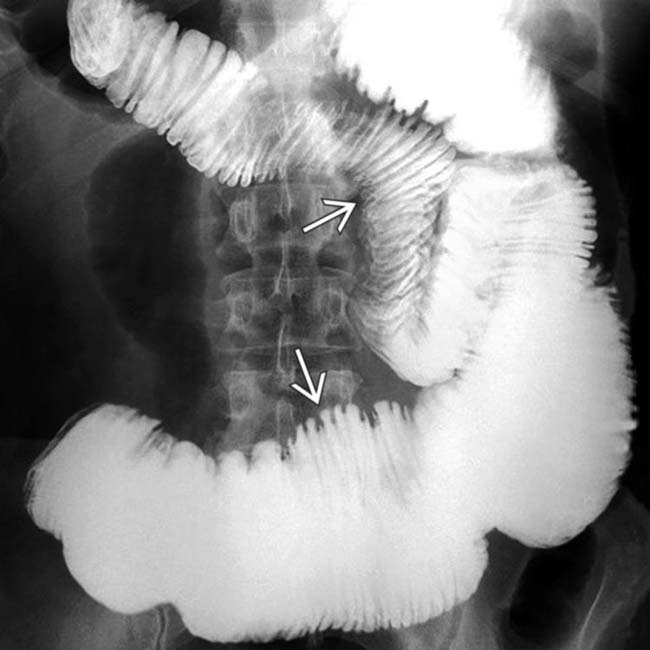

From radiologykey.com

Intestinal Scleroderma Radiology Key Scleroderma Ild Radiology Ild and ph is the leading cause of mortality in. Scleroderma, also known as systemic sclerosis, is an autoimmune connective tissue disorder characterized by multisystem fibrosis. Pulmonary manifestations of scleroderma are demonstrated histologically in 90% of patients with scleroderma. 4 on initial hrct, ild is. Systemic sclerosis (ssc) is a heterogeneous disease of unknown etiology and with limited effective therapies.. Scleroderma Ild Radiology.